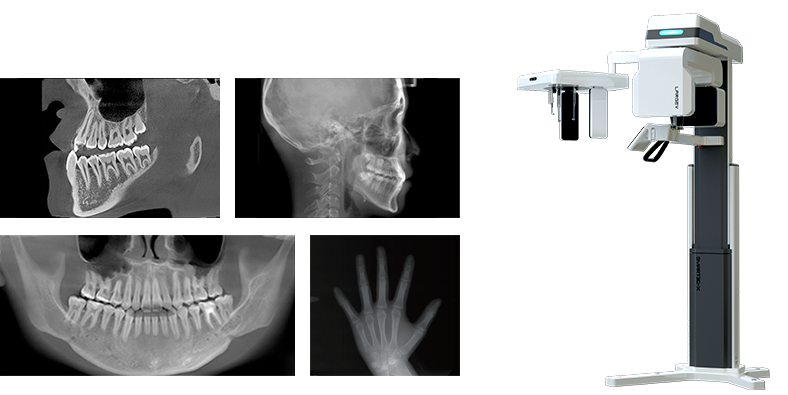

LargeV Instrument Corp., Ltd., fondée en 2011, se distingue par son expertise dans la conception et la fabrication d’équipements médicaux de haute qualité, notamment dans le domaine du CBCT dentaire, de l’imagerie dentaire et de la radiologie orthodontique. Soutenue par une équipe technique issue de l’Université de Tsinghua, elle met l’accent sur l’innovation et la qualité. Récemment, plusieurs de ses produits ont obtenu la certification européenne MDR.